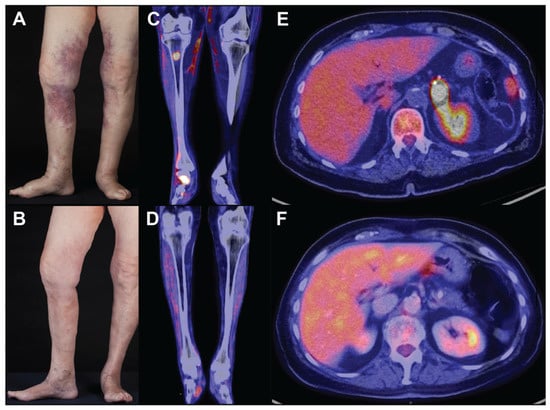

Cutaneous symptoms are more common in the Western variant and have a preponderance for females [28]. The clinical image encompasses erythematous patches and plaques, frequently affecting the lower extremities or trunk. The findings are usually accompanied by general malaise and recurrent fevers. The authors saw a case of a 77-year-old Caucasian female patient presenting with a three-month history of painful lividly discoloured contusiform nodular lesions on both thighs and lower legs (Figure 1A,B). Abdominal and lumbar back pain had initially raised the suspicion of a rheumatologic condition and led to extensive imaging showing no specific pathologies. Additionally, chronic inflammatory bowel diseases had been ruled out, as the cutaneous manifestation of Crohn’s disease can have a similar clinical presentation. Skin lesions of IVLBCL can be accompanied by pain, telangiectasia, and significant oedema adjacent to the lesions. The latter two features should be distinguished from Pseudo–Kaposi sarcoma possibly observed on the lower legs in a background of chronic venous insufficiency of the elderly. Contusiform lesions of IVLBCL must not be confused with erythema nodosum, traumatic panniculitis, or deep-seated hematoma. Other differentials may include lupus profundus, systemic vasculitis, alpha-1-antitrypsin deficiency, subcutaneous panniculitis-like T-cell lymphoma, eosinophilic fasciitis, autoinflammatory syndromes, or reactive angioendotheliomatosis. (Table 2).

Imaging is of paramount importance to determine the affected organ systems and body sites. The modality of choice is fluorodeoxyglucose (18F) (18F-FDG) positron emission tomography-computed tomography (PET-CT), as IVLBCL is highly FDG-avid, and affected sites will be identified with high sensitivity. Furthermore, the intensity of FDG uptake can indicate the response to treatment (Figure 1C–F) [48,49].

Figure 1. Macroscopic findings in IVLBCL: (A,B) cutaneous lesions before (A) and after (B) two cycles of R-CHOP; (CF) PET-CT scans of cutaneous and osseous lesions of the legs before (C) and after (D) six cycles of R-CHOP. Adrenal gland lesion before (E) and after (F) six cycles of R-CHOP. PET-CT scanning showed increased uptake of fluorodeoxyglucose (18F-FDG) in the subcutaneous tissue of both legs, the right tibia, various osseous structures of the right foot (maximal standardised uptake value (SUVmax) = 3.0–21.5), and a nodular lesion in the left adrenal gland (SUVmax = 31).